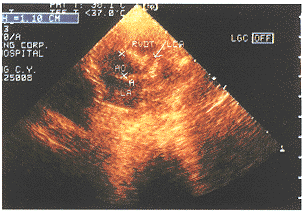

LCA:左冠状动脉(箭头指处),AO:主动脉,RVOT:右室流出道

图1 患儿女,6个月,发病后20天,左冠扩张

LCA:左冠状动脉(箭头指处),AO:主动脉

图2 同一患儿两年后,左冠内径正常

58例川崎病患儿经大剂量免疫球蛋白和阿司匹林等治疗,30例无冠脉改变的,用药3个月后即停药观察,未再发现冠脉病变。28例冠脉病变,用药至冠脉正常后3个月,其中5例冠脉扩张持续1年(图1、2),3例冠状动脉瘤,1例发病后2个月夜间猝死于家中,可能为冠脉栓塞或瘤破裂,另2例在1~3年内恢复到正常。2例左冠狭窄,1例11个月恢复正常,另1例服阿司匹林及潘生丁等2年后仍未见改变即停药观察,现已3年,左冠内径1.2mm,右冠内径1.9mm,患儿无临床症状。治疗过程中,我们发现6例患儿有一过性轻度二尖瓣返流,14例左室舒张功能降低,均在3个月内恢复到正常。而各心腔及大动脉内径与左室收缩功能未见明显改变。